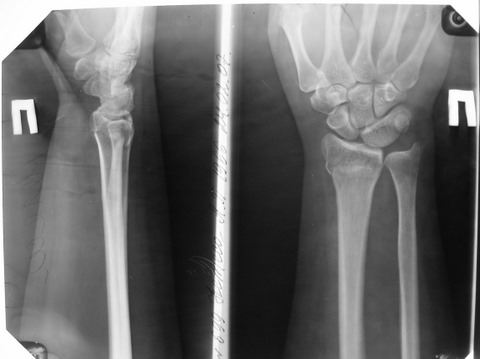

Обратилась женщина 45лет, профессия - швея, травма 24.02.07

вколоченный перелом правого луча (см Ргр Р******279). Лечилась:

На данный момент женщину беспокоят слабокупирующиеся боли

плечо-локоть-кисть по локтевой поверхности больше, ограничение

движений в л\з суставе и мелких суставах кисти (см приложения: общий

вид, объем движений  - рис. Р*******272, Р******271), на Ргр нарастают

явления остеопороза, не смотря на прием препаратов кальция(рис.

Р****277,278).